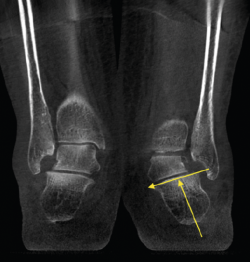

Lesiones de la sindesmosis

En la articulación tibioastragalina, la estabilidad de la articulación de la sindesmosis es un aspecto importante para evitar la aparición de lesiones articulares o artropatía progresiva.

En un contexto postraumático, la valoración de la afectación o la inestabilidad de la misma tiene su importancia para los resultados finales y los posibles tratamientos.

En la cuantificación del desplazamiento y de la inestabilidad de la sindesmosis es importante poder explorar la extremidad contralateral y la valoración en carga de los 2 tobillos.

Los estudios fisiológicos con TAC en carga muestran que el peroné presenta una rotación externa y un desplazamiento posterior con la carga(13).

La valoración inter- e intraobservador en lesiones traumáticas de la sindesmosis es mejor con la TAC en carga que con otros métodos diagnósticos(14,15).

Figura 2. Severo pie plano valgo bilateral con pinzamiento fibular.

- Pie plano valgo del adulto. Permite la valoración de la articulación subtalar, el valgo del retropié y la inestabilidad de la columna medial (Figuras 2 y 3).

- Alteración-inestabilidad de la sindesmosis. Permite el estudio comparativo de la estabilidad de la sindesmosis (Figuras 7 y 8).